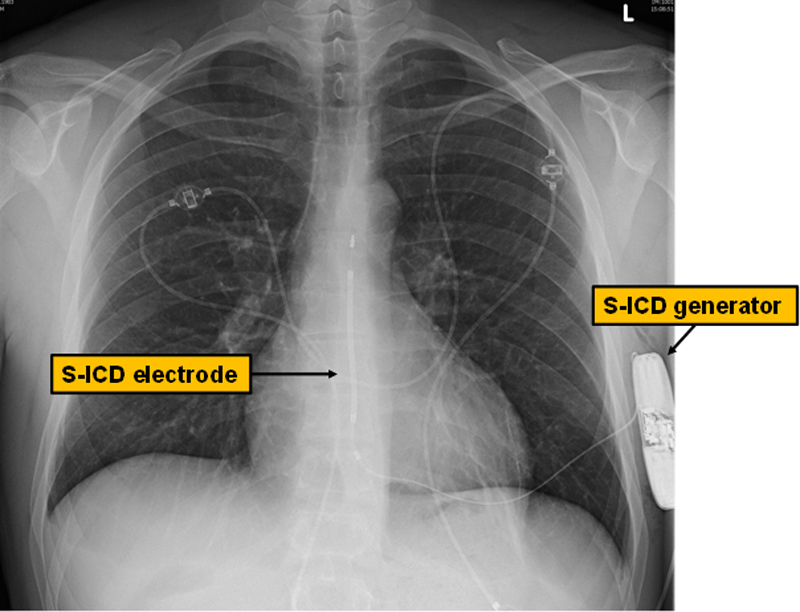

To address these shortcomings of transvenous ICDs, a totally subcutaneous ICD system (S-ICD) was developed, which was approved for use in Europe in June 2009 [17]. This device is typically placed in a pocket between the anterior and mid-axillary line at the level of the apex of the left ventricle, while the S-ICD electrode is tunnelled subcutaneously from the device pocket to ≈1 cm above the xiphoid process, and subsequently cephalad towards the substernal notch (fig. 1) [18]. In contrast to traditional transvenous ICDs, the S-ICD is located completely in the extravascular (and even extrathoracic) space. Therefore, the typical risks associated with transvenous leads such as pneumothorax, cardiac perforation and endocarditis are practically nonexistent or substantially reduced (such as for system infection). Furthermore, the S-ICD lead is more stable and therefore less prone to dysfunction, since its design is different from that of transvenous leads [19].

Figure 1 Chest X-ray of a male patient after S-ICD implantation. The generator of the S-ICD is shown on the left side of the patient together with the electrode, which is tunnelled subcutaneously from the generator to the xiphoid area and towards the suprasternal notch.